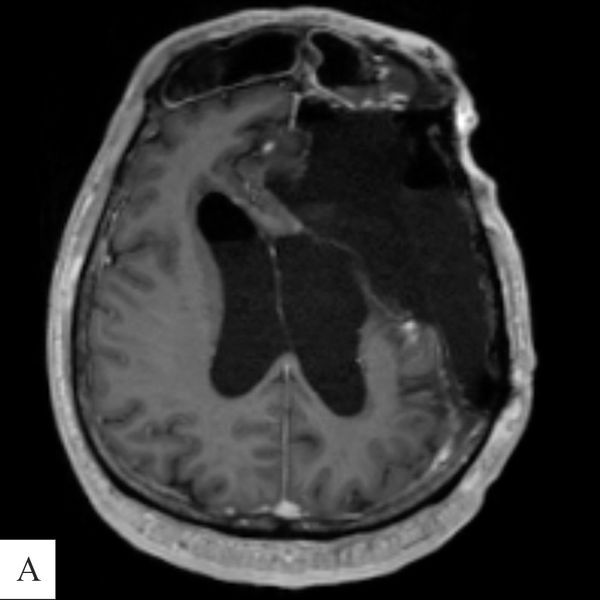

Результаты контрольной МРТ головного мозга с контрастированием: на стыке оснований левой лобной и височной долей ложе удалённой менингиомы размером 6,5 × 4,8 × 6,2 см, заполненное ликвором (спинномозговой жидкостью). По медиальной (внутренней) поверхности ложа виден тонкий ободок изменённой ткани толщиной до 0,9 см. При контрастном усилении нет участков, где бы патологически скапливалось контрастное вещество.

После операции ухудшения состояния и появления новых неврологических симптомов не было.